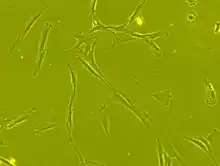

سلولهای بنیادی مزانشیمی (به انگلیسی: Mesenchymal stem cells (MSCs)) که به عنوان سلولهای مزانشیمی استرومایی (به انگلیسی: Mesenchymal stromal cells) نیز شناخته شده میشوند سلولهای چند توانی هستند که میتواند به انواع سلولها از جمله سلولهای استئوبلاست (سلولهای استخوانی)، کندروسیت (سلولهای غضروفی)، میوسیت (سلولهای عضلانی) و سلولهای چربی تمایز پیدا کنند.[1][2][3]

اکثر تکنیکهای کشت مدرن هنوز هم بر طبق روش colony-forming unit-fibroblasts میباشند.[10]